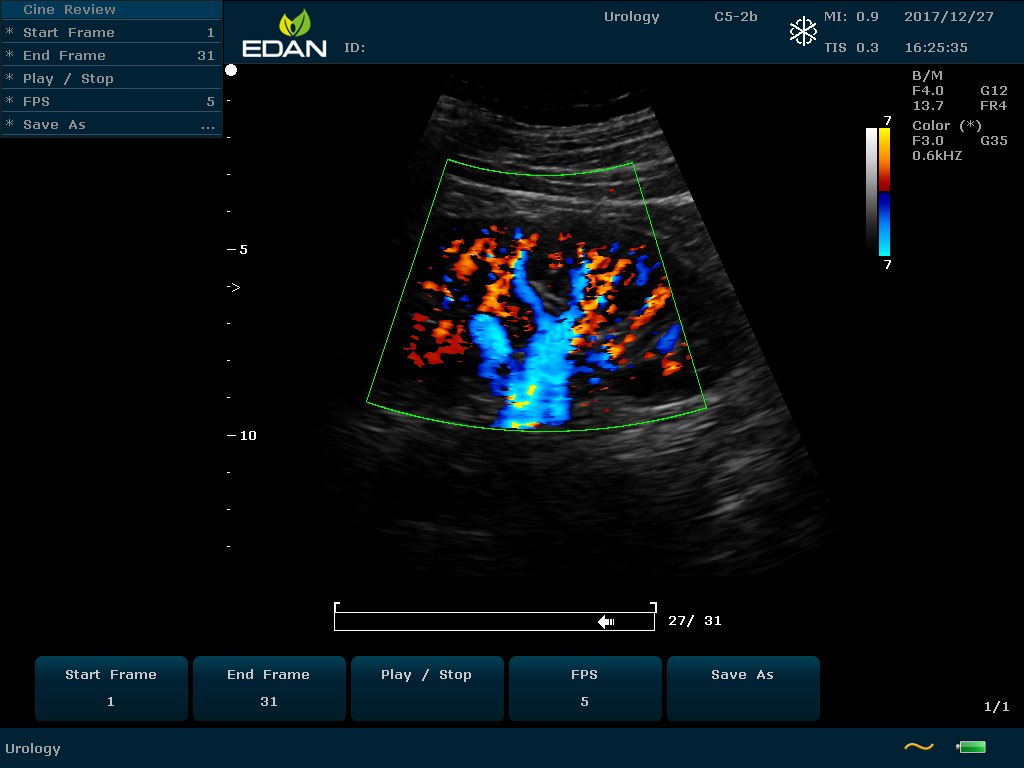

Особенность U60 Edan — расширенное применение. Ультразвуковой аппарат рекомендован для абдоминальных исследований, гинекологии и акушерства, кардиологии, педиатрии, урологии, изучения малых органов, сосудов. Для U60 Edan используются конвексные, линейные, фазированные и внутриполостные датчики.

Передовые технологии позволяют повысить качество визуализации в несколько раз. УЗИ-аппарат U60 Edan отличается возможностью быстрой настройки визуализации. Специальные функции позволяют моментально отображать данные за счет быстрой оптимизации параметров. Режимы визуализации: B-mode, M-mode, Color Doppler, Power Doppler Imaging, Pulsed Wave Doppler, Continuous Doppler.

• Цветовое Допплеровское картирование

• Импульсная Допплерография

• Направленная энергетическая Допплерография